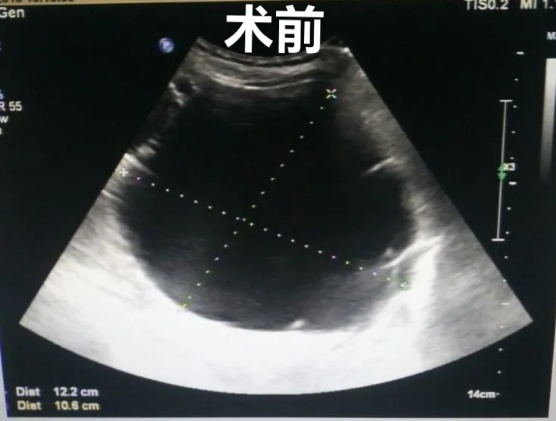

肝囊肿经皮超声引导性介入治疗

2、超声引导下囊肿抽液硬化治疗,肝囊肿、肾囊肿穿刺抽液硬化治疗,盆腔囊肿穿刺抽液硬化治疗,甲状腺、乳腺囊肿穿刺抽液治疗。

3、超声引导下置管引流,胸腹水穿刺及置管引流、心包积液穿刺置管引流、脓肿穿刺置管引流。